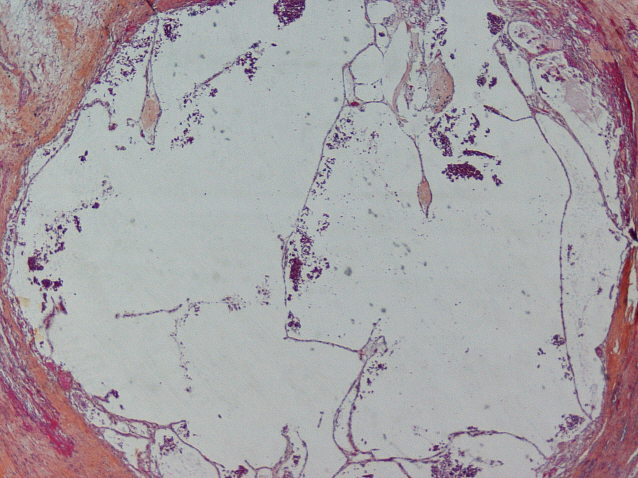

Renal tumor grading

Case ID: 593